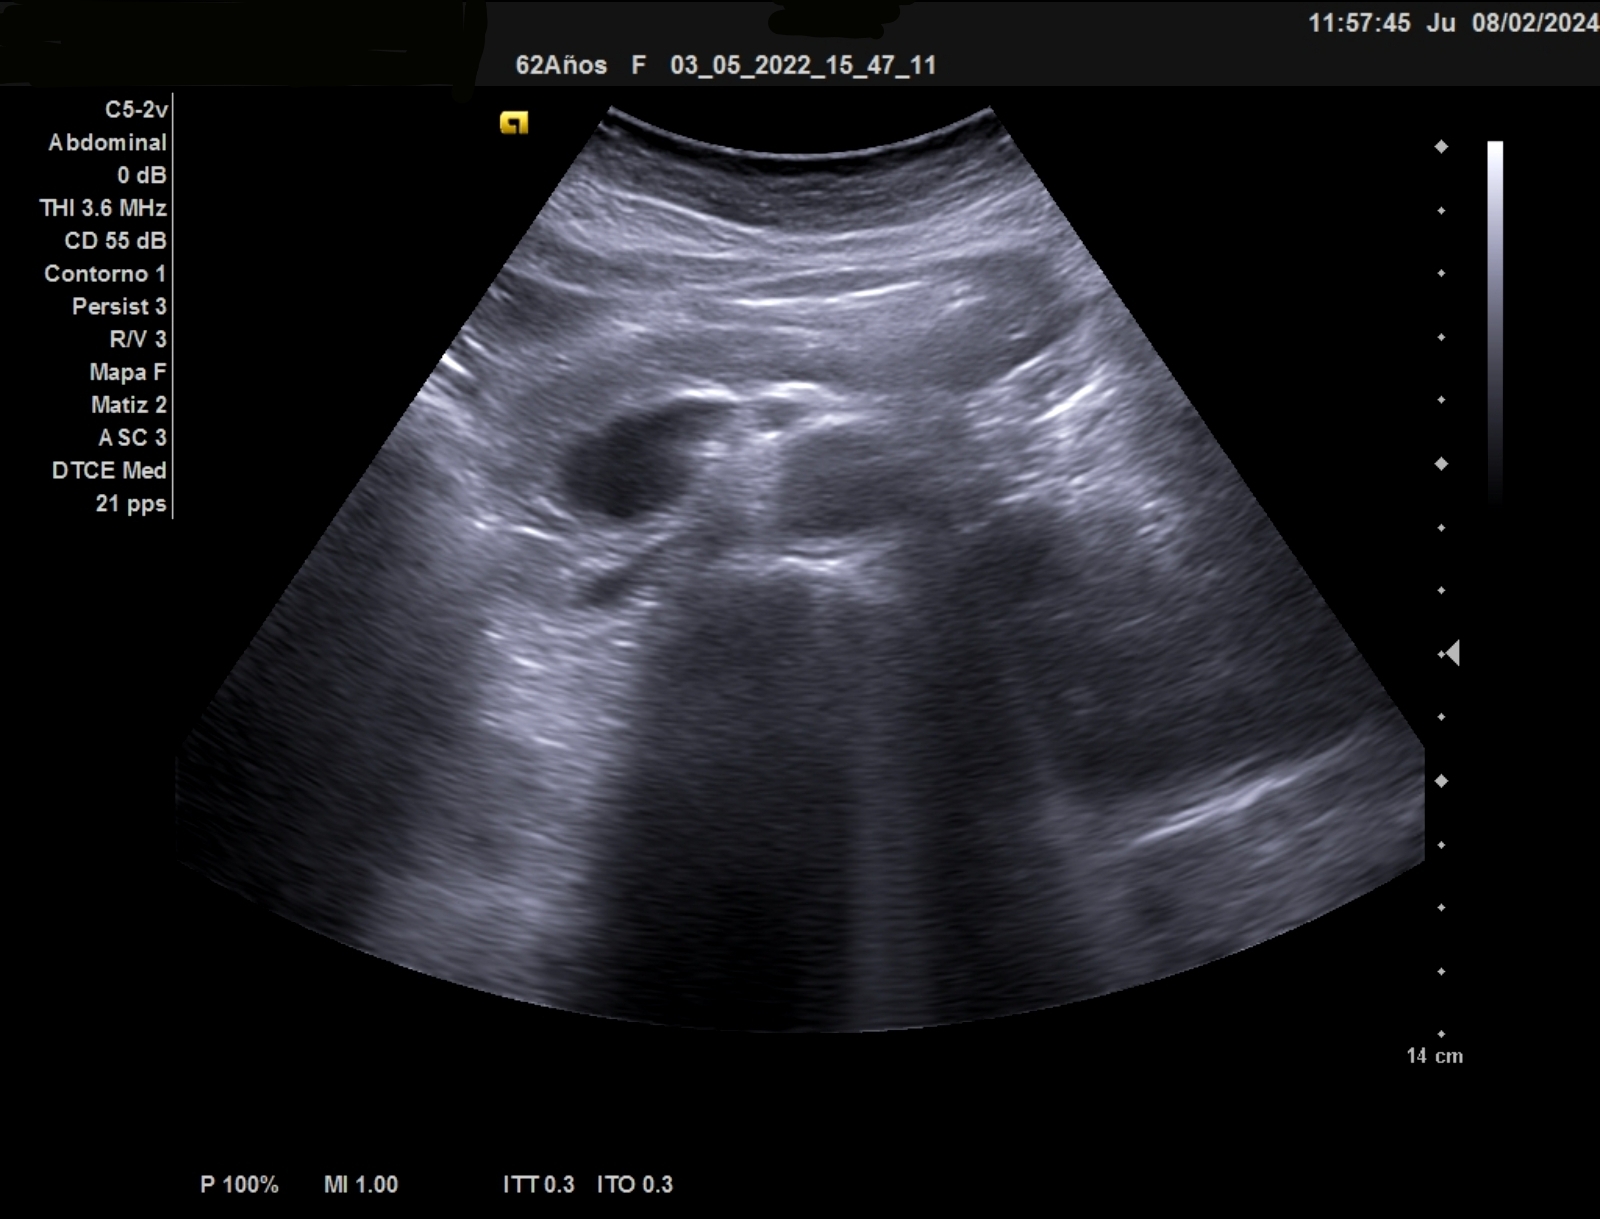

Ecografía clínica: Esplenomegalia con bazo de 12,6 mm eje longitundinal, 9,5 mm transversal y un area 71 cm2 (patológico por encima de 55)

La ecografía clínica debe ser exhaustica, a nivel de hipocondrio izquierdo debe localizarse el bazo con inspección del parénquima, bordes e hilio, debe medirse los 2 diámetros y a eso añadir el area. Se considera patoñogico un diámetro por encima de 12 mm eje longitudinal, >5mm eje transversal y el area por encimad e 55 cm2. En casos de gran esplenomegalia orientará hacia etiología infecciosa: parasitaria, vírica o bacteriana.

Ante la detección de una alteración en el hemograma como la bicitopenia, nos planteamos la ecografía para complementar la ananmesis y la exploración física. La ecografía abdominal debe ser sistemática y exhaustica, inspeccionando las visceras en su totalidad. En el hipocondrio izquierdo puede ser una compleja la visualización completa del bazo. Deben medirse en sus 3 ejes incluyendo el área.